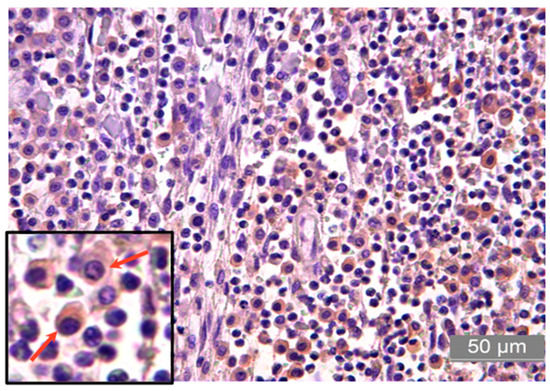

2.2. Cytology and Histopathology Analyses

3.2. Immunolabeling of Proteins PD-L1, CTLA-4, RANK, RANK-L, and IFN-γ